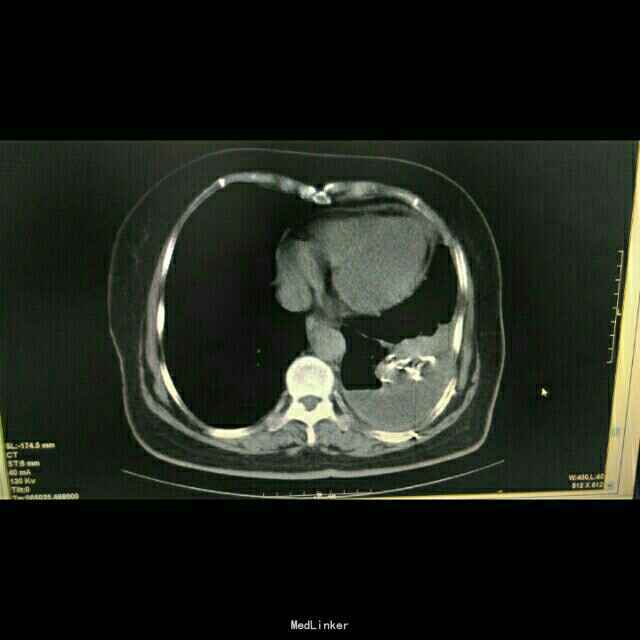

查体:体温:36℃,脉搏:86次/分,呼吸:21次/分,血压:137/81mmHg,胸廓无畸形,两侧对称,双肺呼吸动度一致,左下肺呼吸音减弱,未闻及干湿罗音。心率:86次/分,律齐,心前区及各瓣膜听诊区未闻及杂音,腹软,无压痛及反跳痛。双下肢体无水肿。 辅助检查:胸部CT示:左肺下叶,双肺多发转移灶。于10月16日行左侧胸腔积液穿刺引流,胸水病理检查示:可见少许核异型细胞,考虑为腺癌细胞 颅脑MR检查示:右侧小脑半球两处异常信号,转移瘤可能,右侧放射冠区陈旧性腔梗。

患者治疗后一月余行肺ct检查病灶肺部病灶明显缩小!口服特罗凯治疗耙向治疗!